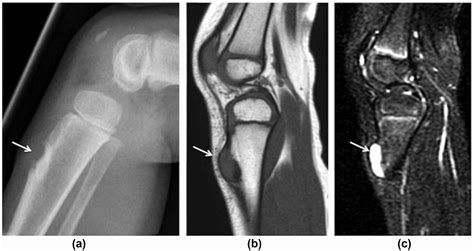

To confirm the diagnosis, physicians utilize a combination of physical examination and diagnostic imaging. Standard X-rays are typically sufficient to view the displacement, but in complex cases, an MRI or CT scan may be ordered to evaluate potential ligament damage or the involvement of the articular cartilage.